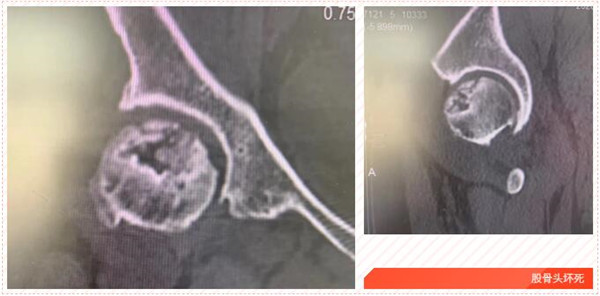

五年前,家住岱山的洪女士發(fā)覺自己的髖部經常疼痛,有時候活動都受影響,特別時久行后更是疼痛難忍,便到我市某院就診,經檢查診斷為“雙側股骨頭壞死”,予以口服藥物等保守治療,可并沒有好轉。

2017年5月,在朋友的建議下,洪女士來到我院,經CT診斷雙側股骨頭無菌性壞死。便在危立軍副院長的建議下,做了左髖關節(jié)置換術。術后,洪女士恢復良好。